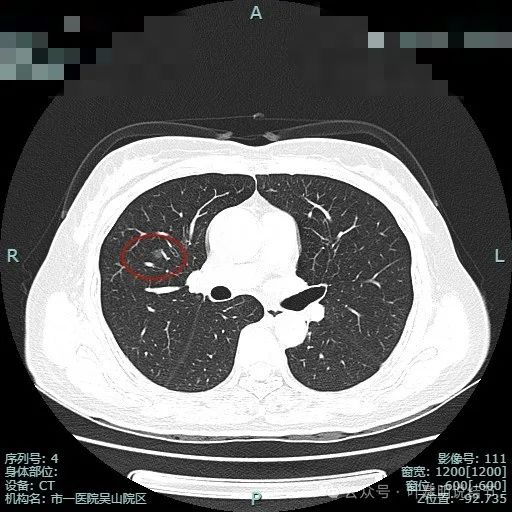

病灶2边缘部分的样子;病灶3有血管贴边,表面不光滑,有微小血管进入。胸膜下另有一微小淡磨玻璃结节,考虑也是肿瘤范畴的,大概是肺泡上皮增生之类(病灶4)。

病灶2几乎不见了;病灶3有血管进入,表面浅分叶,整体轮廓与边界清。

病灶3血管贴边走行。